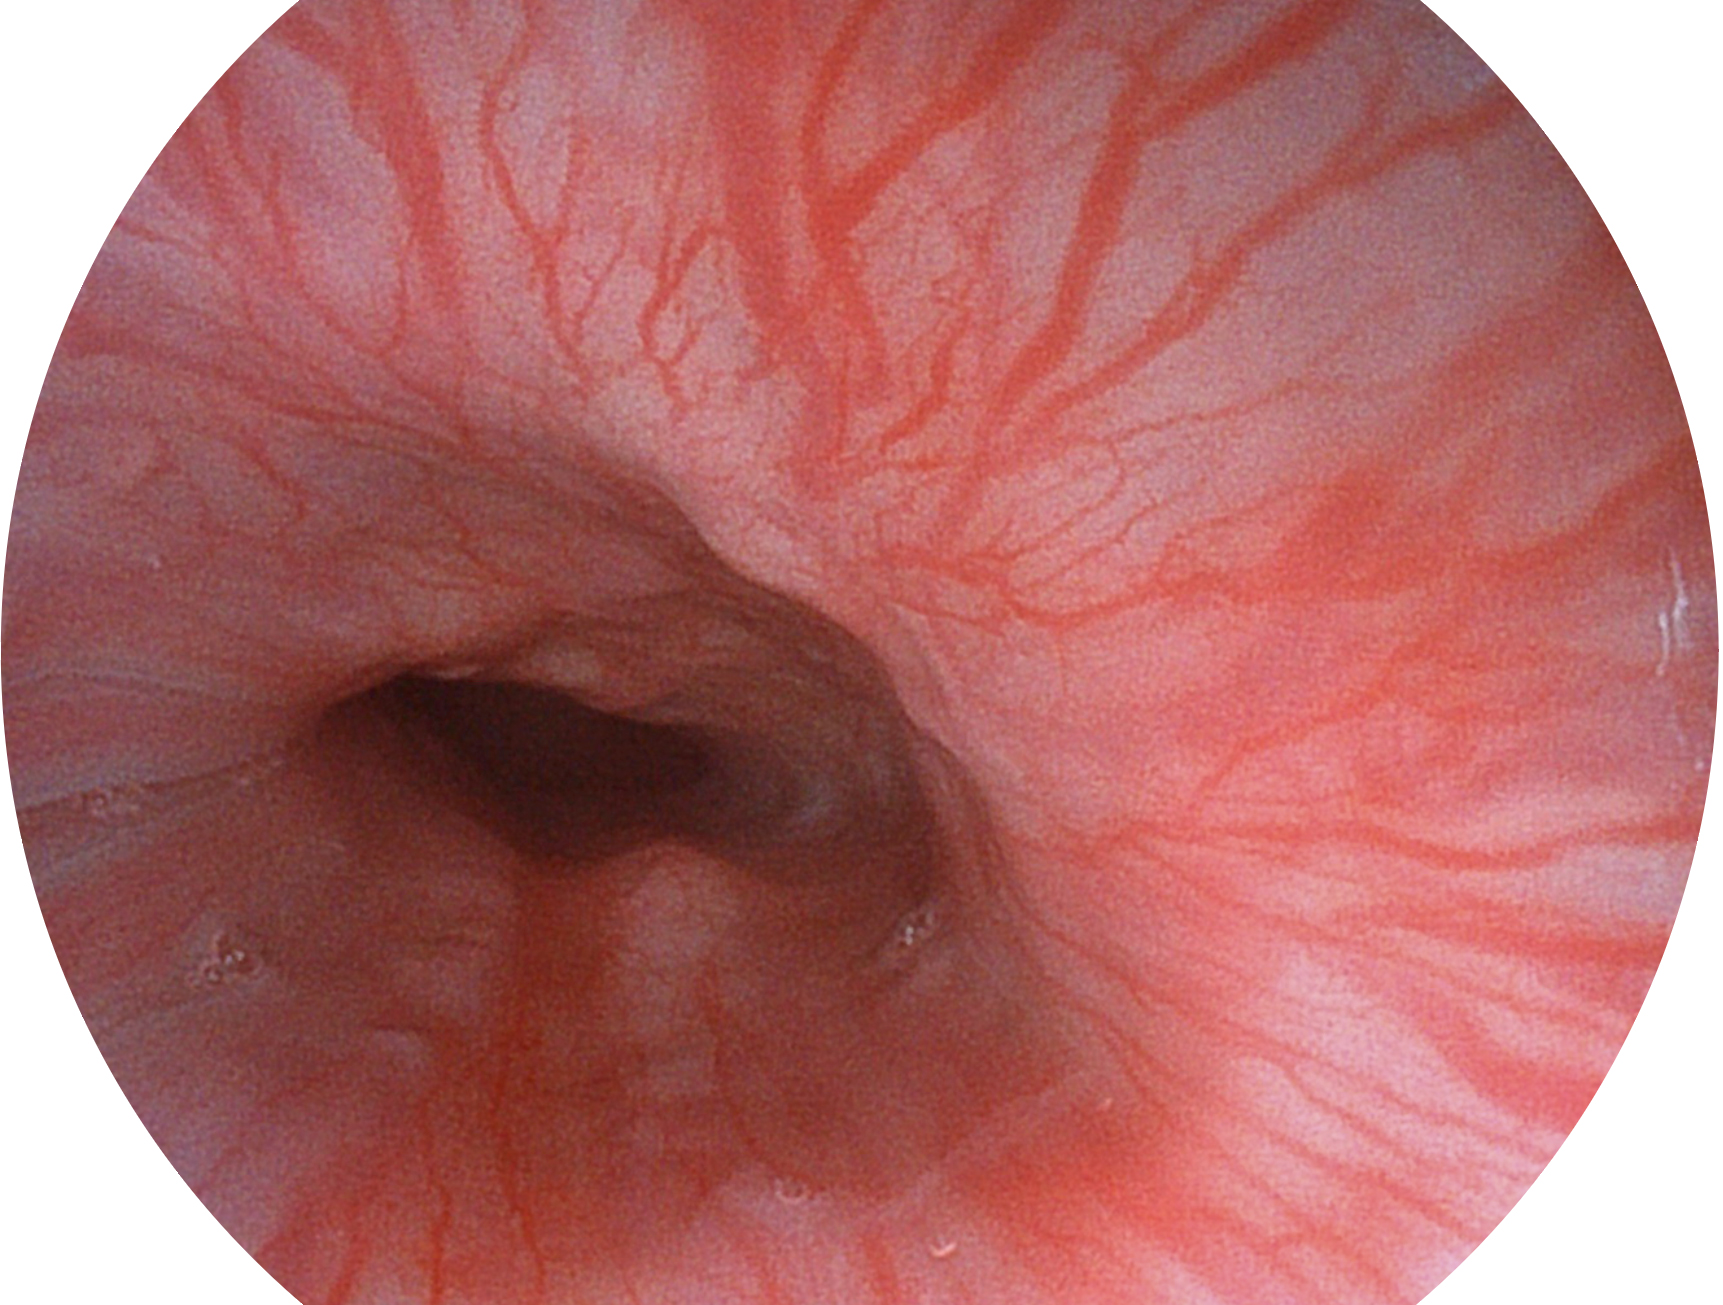

竞技宝(JJB)官方网站新开发的内镜染色技术,主要是基于多波长LED 光源的开发,VLS-55Q 四波长LED 光源是由四个不同颜色的LED光按照相应照明模式所规定的特定发光比例进行合束后形成,合束后形成的照明光的光谱由红光、绿光、蓝光及蓝紫光这四个不同的波段范围构成。具有更高光谱自由度,通过光谱比例的控制,实现了聚谱成像技术,英文全称为“Spectral Focused Imaging, SFI”,缩写为“SFI”和光电复合染色成像技术,英文全称为“Versatile Intelligent Staining Technology, VIST”,缩写为“VIST”。